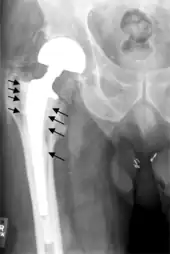

Metal on metal prosthetic hip

Cement-free implant sixteen days after surgery. Femoral component is cobalt chromium combined with titanium which induces bone growth into the implant. Ceramic head. Acetabular cup coated with bone growth-inducing material and held temporarily in place with a single screw.